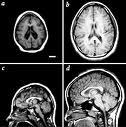

En México anualmente hay alrededor de 100 casos por un millón de adultos entre 25